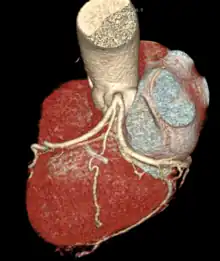

It arises from the right coronary artery in around 60% of individuals, from the left circumflex coronary artery in about 40% of individuals,[1] and in less than 1% of humans, the artery has an anomalous origin directly from the coronary sinus, descending aorta, or distal right coronary artery.

The origin of the sinoatrial node artery is not related to coronary artery dominance, which means the side (right or left) that provides the circulation to the back of the heart. In contrast, the atrioventricular nodal branch, that is the artery that brings blood to the atrioventricular node, depends on coronary artery dominance.